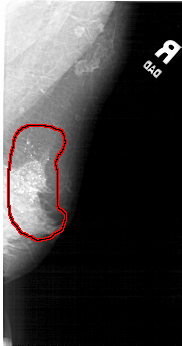

A_1825_1.LEFT_MLO

LEFT_MLO LINES 5491 PIXELS_PER_LINE 2671 BITS_PER_PIXEL 12 RESOLUTION 43.5 NON_OVERLAY

FILE: A_1825_1.RIGHT_MLO.OVERLAY

TOTAL_ABNORMALITIES 1

ABNORMALITY 1

LESION_TYPE CALCIFICATION TYPE PLEOMORPHIC DISTRIBUTION DIFFUSELY_SCATTERED

ASSESSMENT 5

SUBTLETY 5

PATHOLOGY MALIGNANT

TOTAL_OUTLINES 1

BOUNDARY